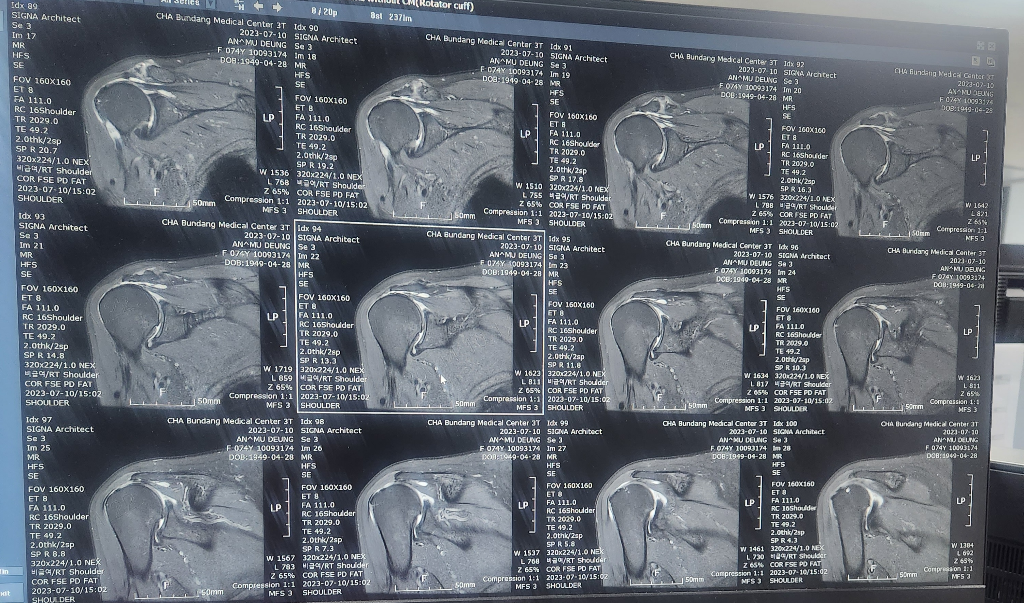

할머니가 넘어지면서 어깨를 다쳤는데

검사만하고 설명은 다음으로 미뤄져서요..

혹시 이 영상만으로 현재 어깨상태 문의드려도될까요

• 2번 째 사진

현재 어깨관절에 물이 차있는 소견으로 염증이 있는 것으로 보이며, 회전근개의 경우는 영상의 크기가 작아 정확한 판단은 어렵겠습니다.